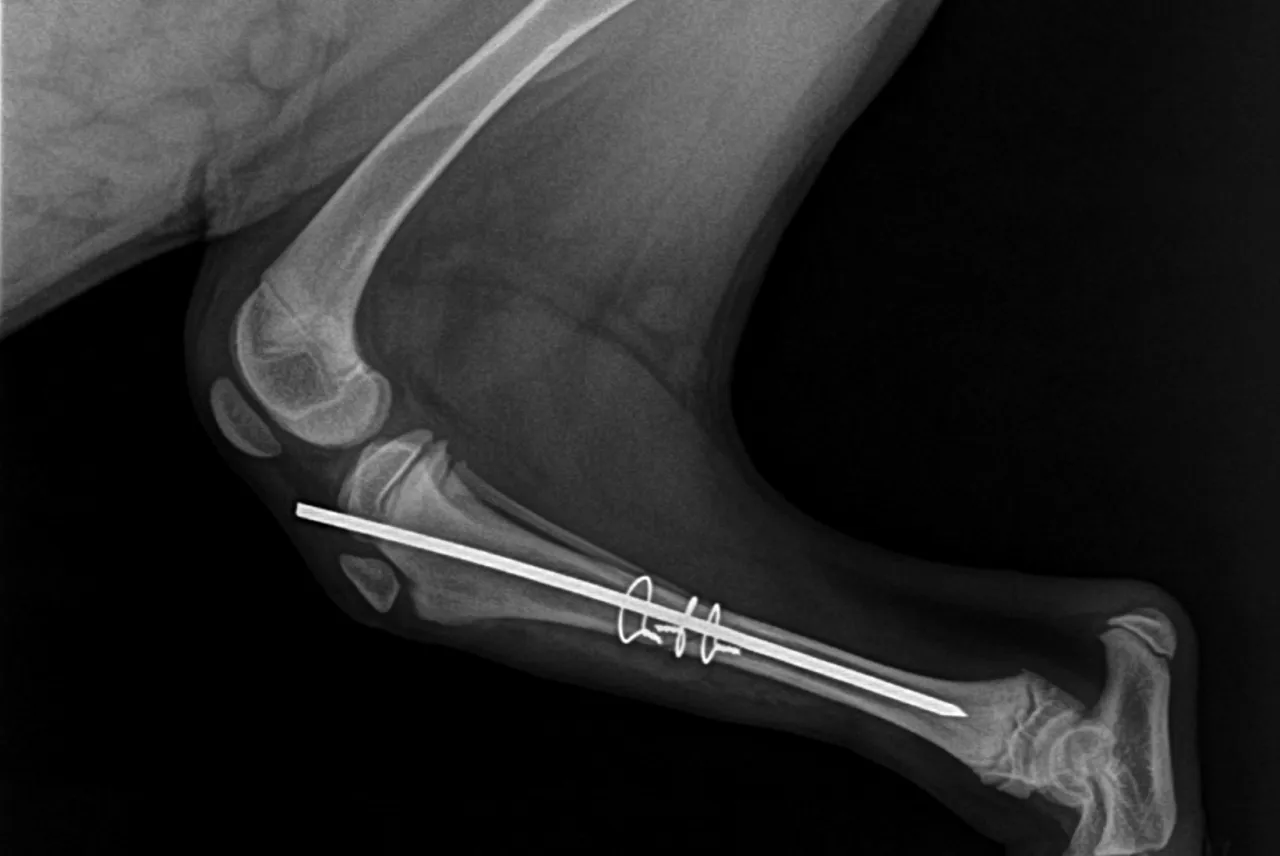

Rola badań obrazowych: dlaczego RTG jest niezbędne, chociaż nie widać na nim więzadła?

Po badaniu klinicznym weterynarz zazwyczaj zleci badania obrazowe, przede wszystkim zdjęcia rentgenowskie (RTG). Wiele osób dziwi się, dlaczego wykonuje się RTG, skoro na zdjęciu rentgenowskim nie widać samego więzadła (jest to tkanka miękka, niewidoczna na standardowym RTG). Odpowiedź jest prosta: RTG jest niezbędne z kilku powodów. Po pierwsze, pozwala ocenić zmiany zwyrodnieniowe w stawie, które często towarzyszą zerwaniu więzadła, zwłaszcza w przypadkach przewlekłych. Po drugie, umożliwia wykluczenie innych schorzeń, takich jak złamania, zwichnięcia czy nowotwory kości, które mogą dawać podobne objawy. Po trzecie, w przypadku planowania operacji, zdjęcia RTG są kluczowe do dokładnego zaplanowania zabiegu, szczególnie w nowoczesnych technikach, takich jak TPLO czy TTA, gdzie precyzyjne pomiary kątów i struktur kostnych są absolutnie konieczne. Czasami, w bardziej skomplikowanych przypadkach, może być również zlecone USG lub rezonans magnetyczny, ale RTG jest zazwyczaj pierwszym krokiem.

- TPLO (Osteotomia poziomująca plateau kości piszczelowej): To jedna z najnowocześniejszych i najskuteczniejszych metod, szczególnie dla dużych i aktywnych psów. Polega na zmianie biomechaniki stawu poprzez precyzyjne cięcie i rotację kości piszczelowej. Neutralizuje to siły, które powodują niestabilność, eliminując potrzebę samego więzadła. Jest to technika wymagająca specjalistycznego sprzętu i doświadczenia chirurga, stąd jej wyższa cena.

- TTA (Wysunięcie guzowatości kości piszczelowej): Podobnie jak TPLO, zmienia biomechanikę stawu. Polega na przesunięciu do przodu fragmentu kości piszczelowej (guzowatości), co również stabilizuje kolano. Istnieją różne warianty TTA (np. TTA Rapid), które mogą różnić się kosztem i techniką wykonania.

Wybór metody zależy od wielu czynników, takich jak wielkość psa, jego waga, aktywność, kąt nachylenia plateau piszczeli oraz doświadczenie chirurga. Zazwyczaj metody zmieniające biomechanikę (TPLO, TTA) są droższe, ale oferują lepsze i trwalsze rezultaty, zwłaszcza u dużych psów.